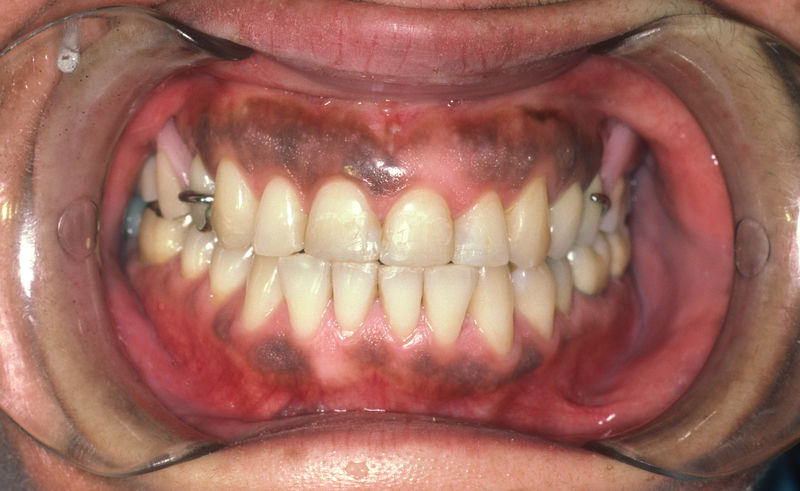

Proceso fundamental y exhaustivo que realiza el odontólogo para identificar la condición de la cavidad oral e identificar tanto zonas que esten sanas como aquellas que no lo son y buscar la causa de cualquier enfermedad o anomalía en la cavidad oral. No se limita a buscar caries, sino que ofrece una evaluación integral que sirve de base para diseñar un plan de tratamiento adecuado, efectivo y personalizado.

Conocida como limpieza dental profesional, es un procedimiento preventivo que se realiza con el objetivo de eliminar la placa bacteriana, el sarro y las manchas superficiales que se acumulan en los dientes y debajo de la línea de las encías, y que no pueden eliminarse con el cepillado ni el uso de hilo dental en casa.

Amplia gama de tratamientos para mejorar la apariencia de la sonrisa, corrigiendo el color, la forma, el tamaño, la alineación y la posición de los dientes. Los procedimientos más comunes y solicitados incluyen el blanqueamiento dental, las carillas y coronas, así como las resinas.

Implantes, ortodoncia y coronas.

Ortodoncia y coronas.